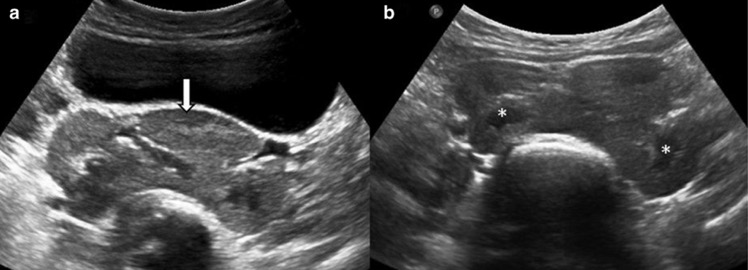

- Colonne proéminente de Bertin